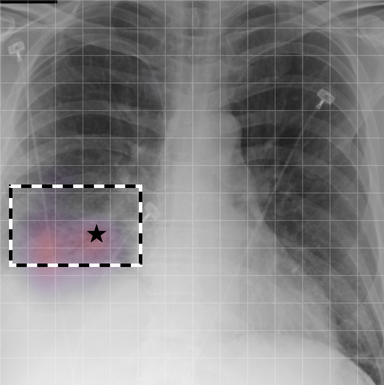

| (1) |

for , where denotes 2D sinusoidal positional encodings [12] and is its temporal counterpart, which is learnt (Fig. 2) [4]. The layer-normalised () [6] output of the final transformer encoder block is an ‘aggregated’ representation of patch-level progression information anchored on the current image. Figure 3 shows attention roll-out [1] applied to after pre-training, showing how the prior image contributes to the fused representation. Figure A.5 further highlights the robustness to variations in pose underlining that registration is not necessary for this encoder.

A.3 Self-attention visualisation

In Figure A.3, we show examples of self-attention rollout [1] maps for pleural effusion and consolidation, including radiologist-annotated bounding boxes surrounding the corresponding pathology in each prior and current image.

To model the attention flow through the transformer encoder block, we first average each attention weight matrix across all heads, subsequently we multiply the matrices between every two layers. For every block we add the identity matrix in order to model the residual connections. Last, we only keep the top 10 of attention weights per block to reduce noise in the final rollout map. In contrast to [21], we do not visualize the rollout map with respect to a [CLS] token. Instead, we choose a reference image patch from the center of the radiologist-annotated bounding boxes, marked with in Figure A.3.

We find that the rollout maps in Figure A.3 are in good agreement with radiologist-annotated bounding boxes, i.e., the reference patch attends to other patches within the bounding boxes in the prior and current image. In addition, we find that BioViL-T is robust to pose variations, e.g., in Figure A.3 (a) we show that despite the vertical shift between prior and current image, the reference patch attends to the correct image patches in the prior image.